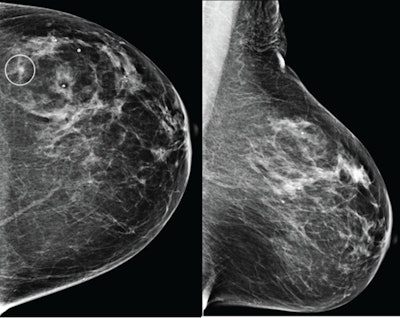

Craniocaudal (left) and mediolateral oblique (right) digital mammography images of the left breast were assessed by interpreting radiologist as BI-RADS category 1, consistent with negative result. The AI system flagged asymmetry in lateral breast on the craniocaudal view (circle) and categorized examination as intermediate risk, consistent with negative or positive result depending on threshold used for categorizing AI results. The patient was not diagnosed with breast cancer within one year after screening examination, consistent with negative outcome according to present study’s reference standard. Thus, interpretation by radiologist was true negative and by AI system was positive if defining both intermediate-risk and elevated-risk categories as positive. Annotation was not generated by the AI system but rather was recreated by present authors based on AI output coordinates.the ARRS.